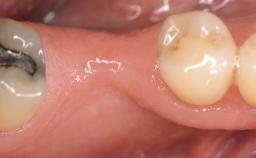

Treatment of Soft-Tissue Fenestration in the Esthetic Zone

This case demonstrates that a connective-tissue graft in combination with a coronally positioned graft is an effective method of treating cases with peri-implant mucositis and an abutment-level sinus abscess. A 42-year-old man presented with a swelling adjacent to an implant crown at site 21. The swelling had been present for approximately three weeks and was constrained to the buccal and palatal gingival aspects of the implant. A discharge was noted on finger pressure, with localized gingival recession present on the mid- and distolabial aspects of the crown.